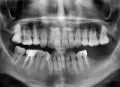

Примерно полторы недели назад поела орехов, и заболела область 7 и 8 зуба справа внизу. Соседняя 6-ка удалена уже давно. Было сделано КТ нижней челюсти, в заключении об этой зоне вообще не упоминается (т.е. рентгенолог вообще ничего подозрительного там не увидел, как я поняла). При очном осмотре врачи также ничего не обнаружили. Единственное, в эмали 8-го зуба, о котором идет речь, с щечной стороны есть некариозная небольшая полость, которую стоматолог предложил мне точечно запломбировать. 7-ка давно точечно запломбирована с щечной стороны.

Так вот: может ли так болеть зуб (или зубы) исключительно вследствие чрезмерной жевательной нагрузки? Я понимаю, что речь идет о гипотезе, все же хочется узнать Ваше мнение. Снимки приложить не могу, т.к. есть только результат КТ на CD.

Скорее нет, причиной не может быть просто жевательная нагрузка. Рекомендую Вам показаться ещё к врачам на очный приём.

Снимок можете открыть на компьютере, сфотографировать область зубов и прикрепить сюда, я прокомментирую.